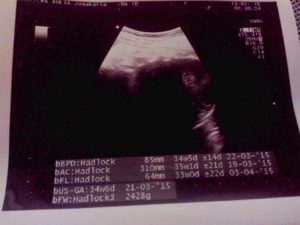

Tanggal 13 Februari 2015, hari ini jadwal nya control si jagoan kembar ke dokter. Dan ini udah masuk usia kehamilan yang ke-34 minggu. Posisi kepala nya sudah di bawah semua. Posisi plasenta nya juga tidak menutupi jalan lahir. Cuma saat itu masalah nya ada di berat badan. Ternyata berat jagoan yang pertama jauh lebih besar dibandingkan dengan berat jagoan yang kedua. Berat jagoan pertama 2.4 Kg sedangkan berat jagoan yang kedua Cuma 1.6 Kg. Saat itu yang di khawatirkan dokter adalah TTS (Twin to Twin Transfusion Syndrome), tapi kalopun terjadi itu kemungkinan nya kecil, karena si jagoan ini masing2 memiliki plasenta. Dengan kata lain plasenta nya sendiri2. Masih belum tau juga saat itu apa penyebab jarak yang terlalu jauh untuk berat nya.

Ini dia Foto USG saat si Jagoan Kembar 34 Minggu